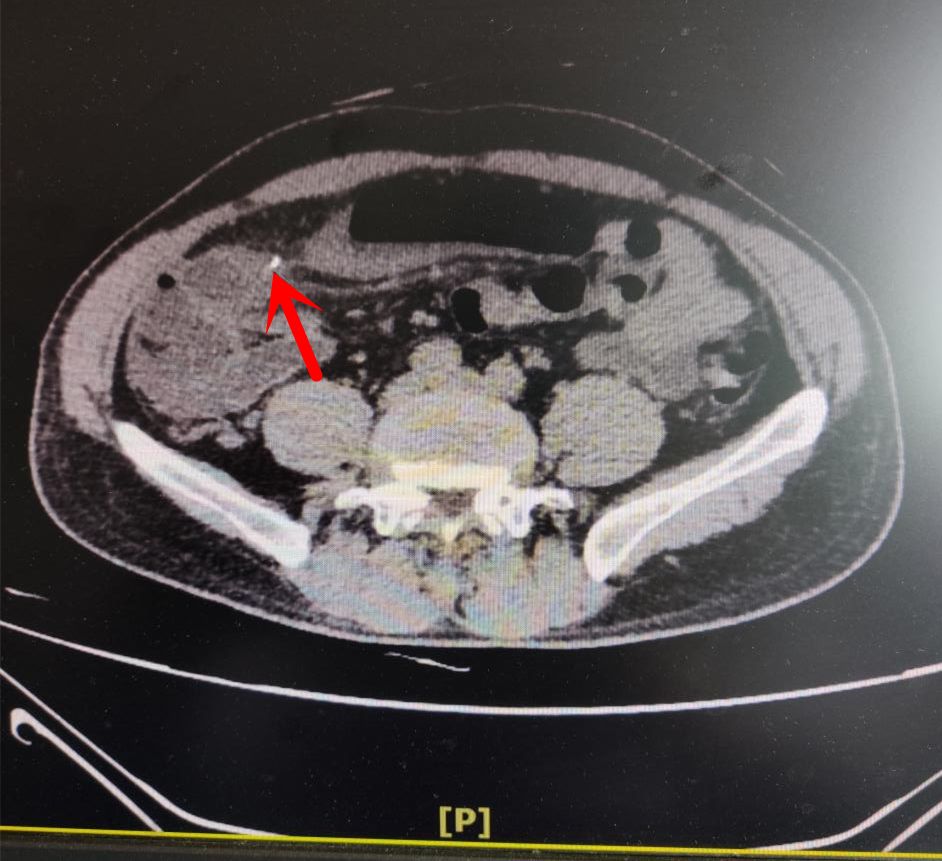

邵东灵官殿一男子吃瓜果致肠穿孔啥情况

图片尺寸1080x520